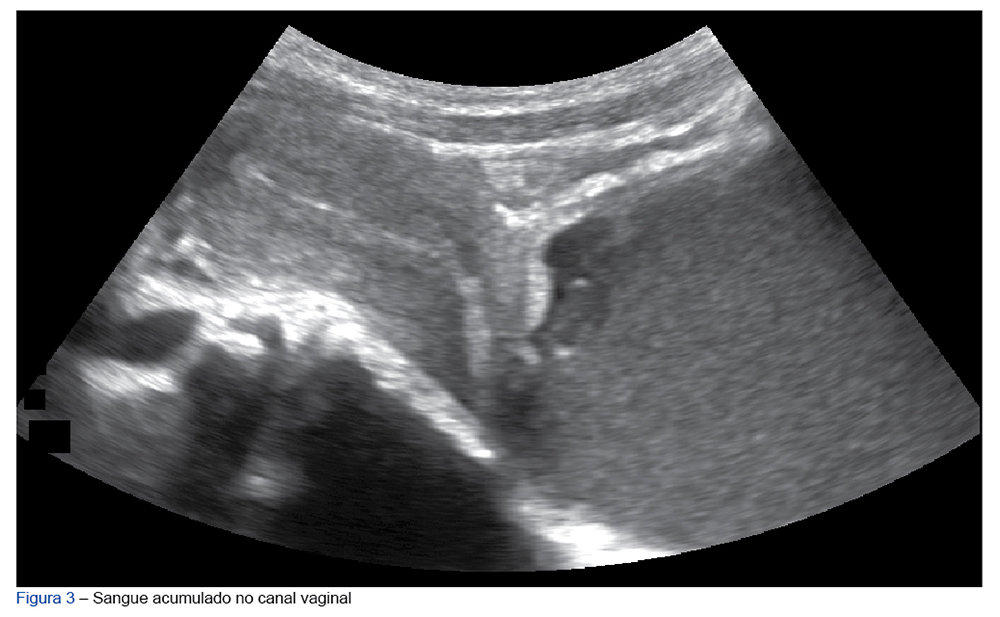

O hematocolpos consiste na obstrução do fluxo menstrual por uma anomalia do trato genital, sendo a mais frequente o hímen imperfurado, uma patologia pouco comum (prevalência de 1:1000  - 1:16 000). Geralmente é uma condição assintomática até a menarca, quando ocorre acumulação de sangue na vagina (hematocolpos) ou no útero (hematometra). Um sintoma raro de hematocolpos é a retenção urinária. Apresentamos o caso de uma adolescente de 12 anos, sem menarca e com estadio sexual de Tanner M4/P5, que recorreu ao nosso serviço de urgência com dor abdominal e retenção urinária. Com o intuito de sensibilizar para esta patologia rara, fizemos uma breve revisão teórica orientada para o rápido diagnóstico e tratamento da mesma.